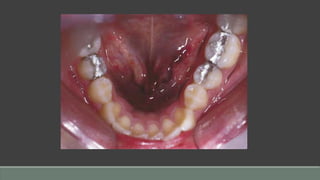

Fissured Tongue

Clinical Presentation

• Multiple crenations or fissures

• May be seen in association with erythema migrans/geographic tongue

• Prominence increases with age

• Usually asymptomatic

• A component of Melkersson-Rosenthal syndrome

• May be a source of halitosis